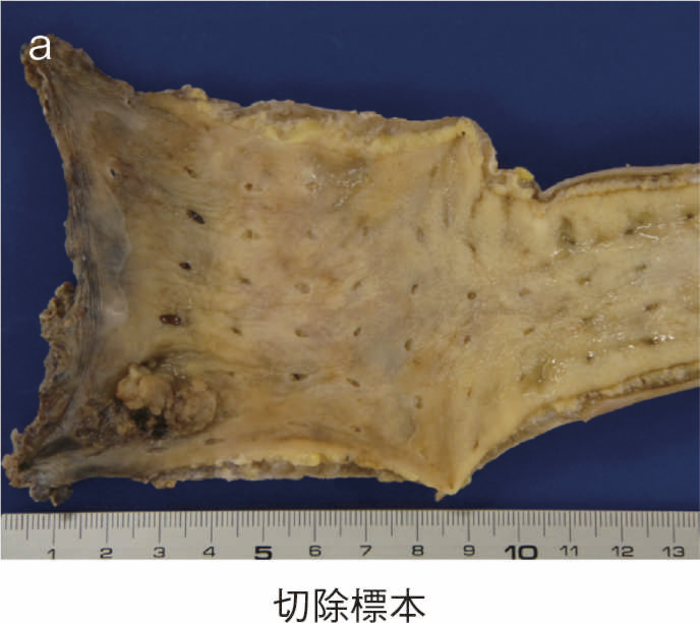

回腸囊と肛門管を器械吻合して肛門管粘膜を温存する術式である。IAAと比べて括約筋機能は良好であるという報告が多い反面,残存肛門管粘膜からの発癌症例もみられ,術後は残存肛門管粘膜に対する内視鏡的サーベイランスが必要である。図17にIACA後に残存肛門管から発癌した症例の切除標本を示す5)。できるだけ残存肛門管粘膜を少なくするために,後壁は歯状線近傍で吻合を行う,double stapling technique(DST)も報告されているが,この術式も体型による影響を受け,肥満体型の男性には低位での吻合は困難である6)。

図17 IACA後の残存肛門管からの発癌症例

この術式は最も罹患歴の長い直腸を温存させる術式であるため,残存直腸の炎症のコントロールの問題だけでなく,直腸からの発癌症例の報告例も増加し,現在では直腸の炎症が軽微な高齢者など,条件を満たす症例以外には行われていない。残存直腸の炎症のコントロールや,残存直腸に対するサーベイランスが必要である。図18にIRA後に残存直腸から発癌した症例の切除標本を示した。